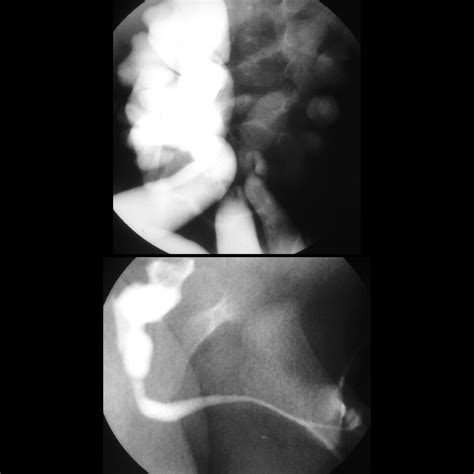

• Voiding cystourethrogram (VCUG): This test involves injecting contrast dye into the bladder and taking X-rays to visualize the urethra and detect the presence of valves.